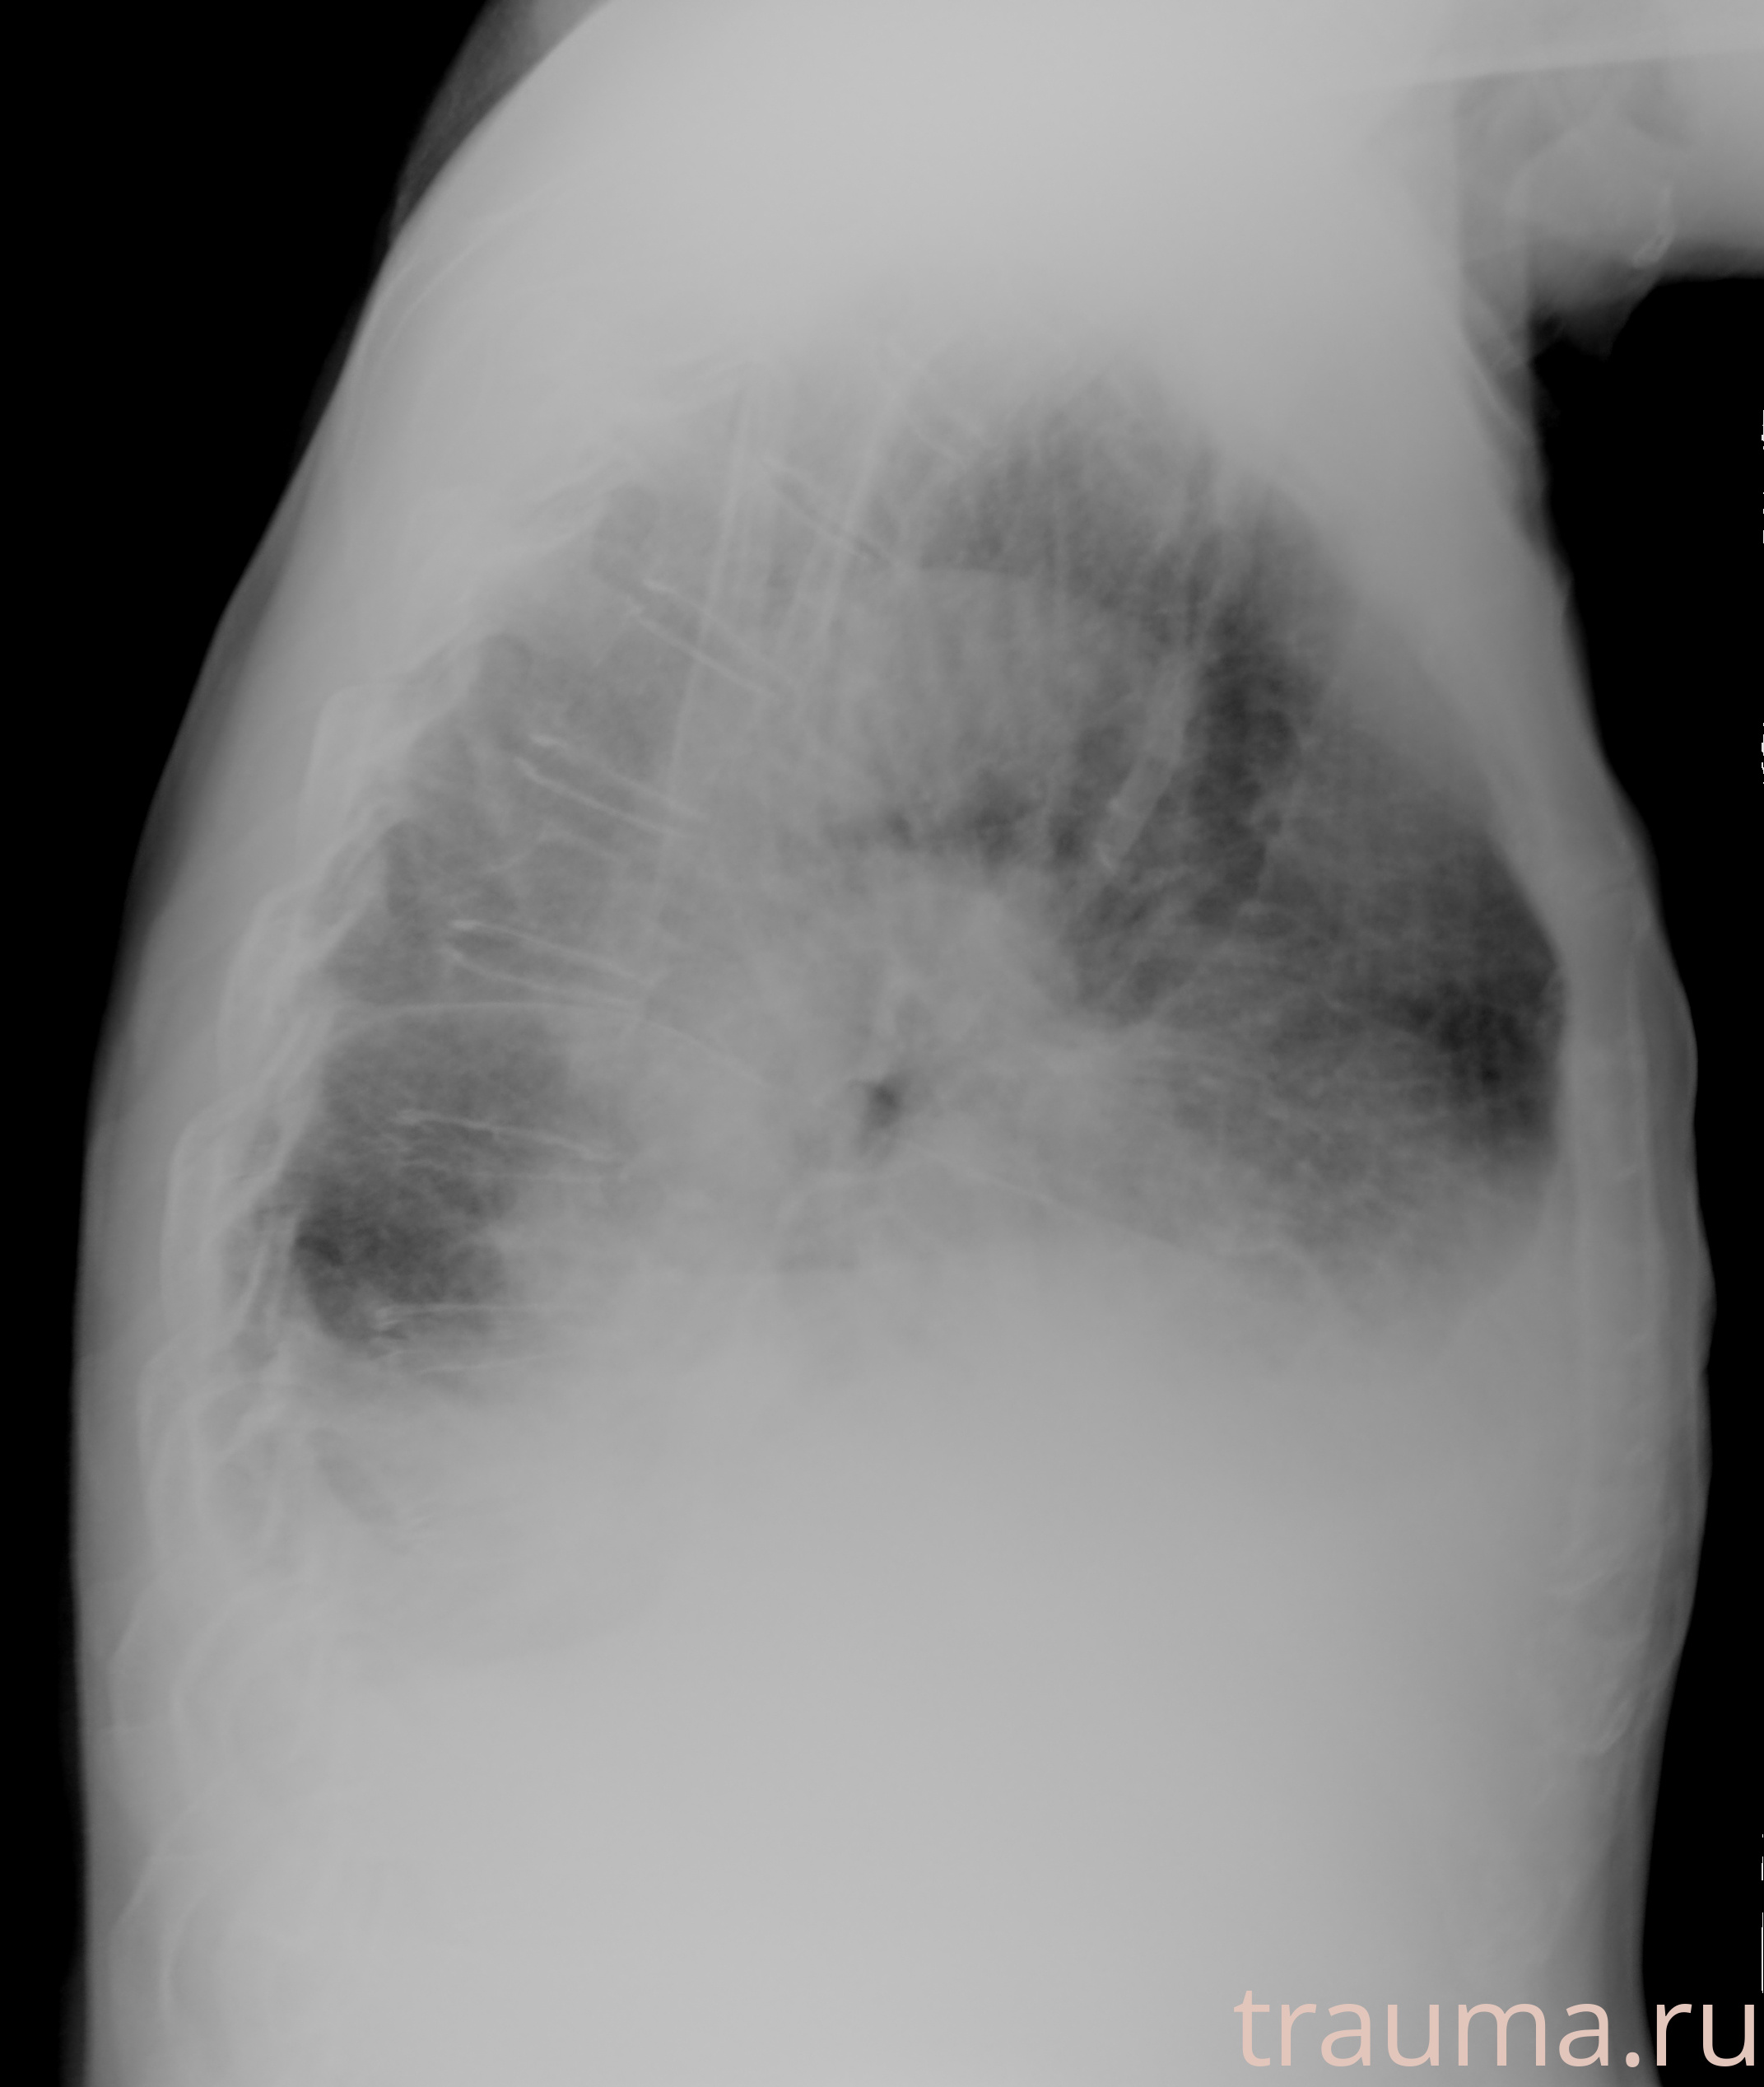

Рентгенограммы

Рентген на дому: по вашему адресу приезжает врач-рентгенолог, травматолог-ортопед с мобильным рентгеновским аппаратом, проводит диагностику травмы или заболевания, делает необходимые рентгенограммы, дает рекомендации по дальнейшему лечению. Получить качественные снимки в домашних условиях возможно благодаря уникальной методике, разработанной МосРентген Центром для института  Склифосовского

при переломе шейки бедра и пневмонии от компании МосРентген Центр - партнера Института имени Склифосовского